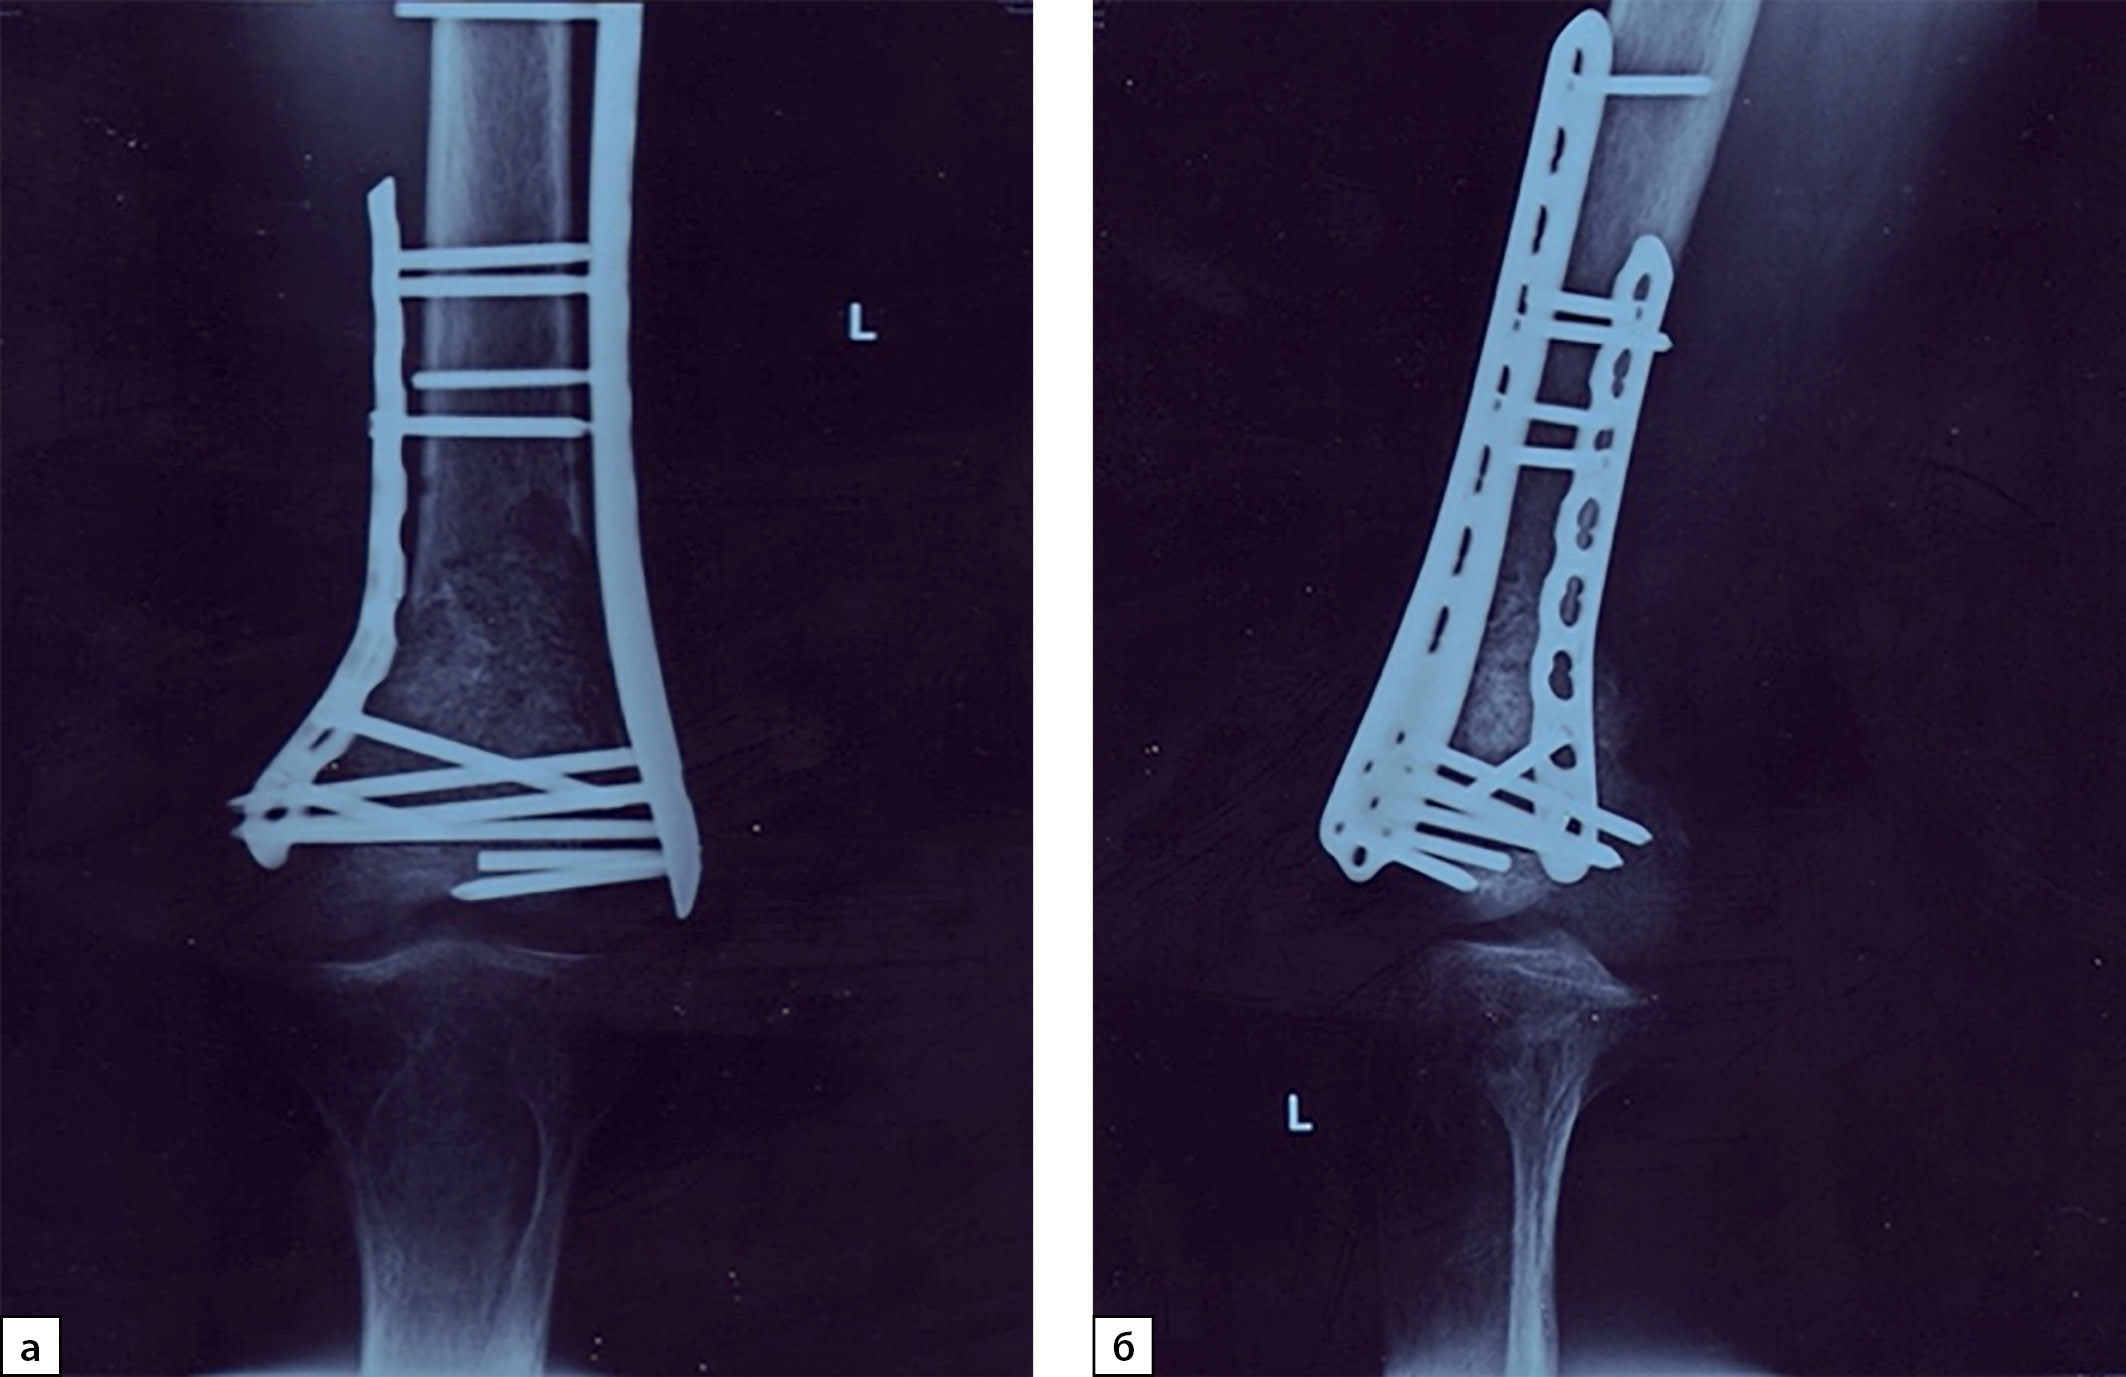

В период прохождения обследования, несмотря на рекомендации, пациент не соблюдал ортопедический режим и при приседании отметил резкую боль в левом бедре, при обследовании диагностирован закрытый патологический надмыщелковый перелом левой бедренной кости. Проведена открытая репозиция перелома, металлоостеосинтез пластинами с аллопластикой дефекта (рис. 4).

Рисунок 4. Рентгенография левого коленного сустава, 2021 г. (в прямой (а) и боковой проекциях (б)): состояние после оперативного лечения — остеосинтеза бедренной кости в нижней трети, аллопластики дефекта.